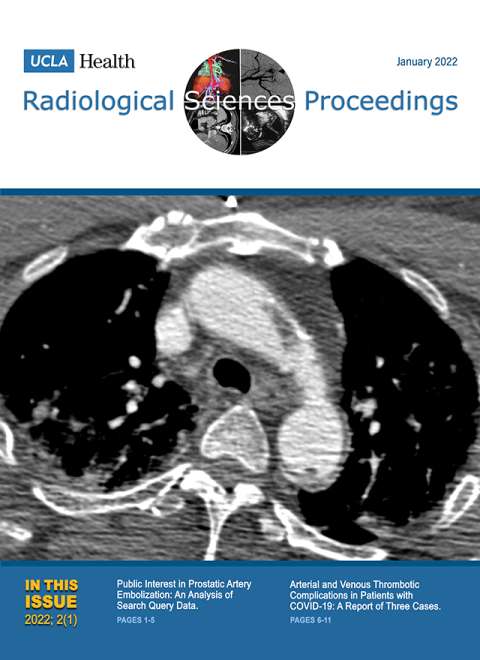

April 2022

Volume 2, Issue 2

- Megacystis-Microcolon–Intestinal Hypoperistalsis Syndrome: A Case Report

- Atrioventricular Discordance with Pulmonary Atresia, Double-outlet Right Ventricle, and Isolated Levocardia: A Case Report of a Rare Congenital Heart Disease

- A Rare Aneurysmal Bone Cyst of the Rib in an Infant: A Case Report